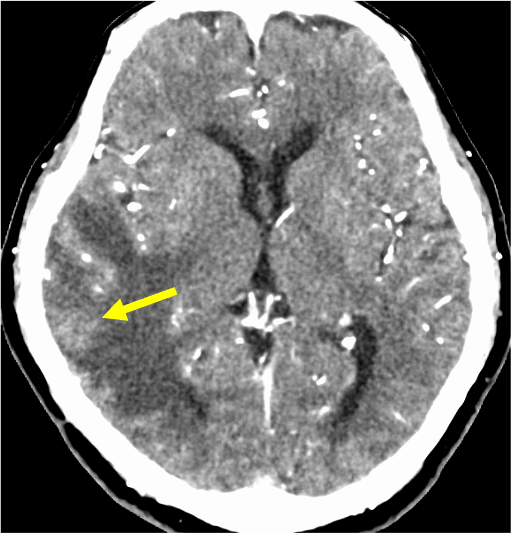

図3.造影CT静脈相

病変はリング状に増強効果あり。還流静脈評価のため、CT venographyのMIP像やVR像を作成した。